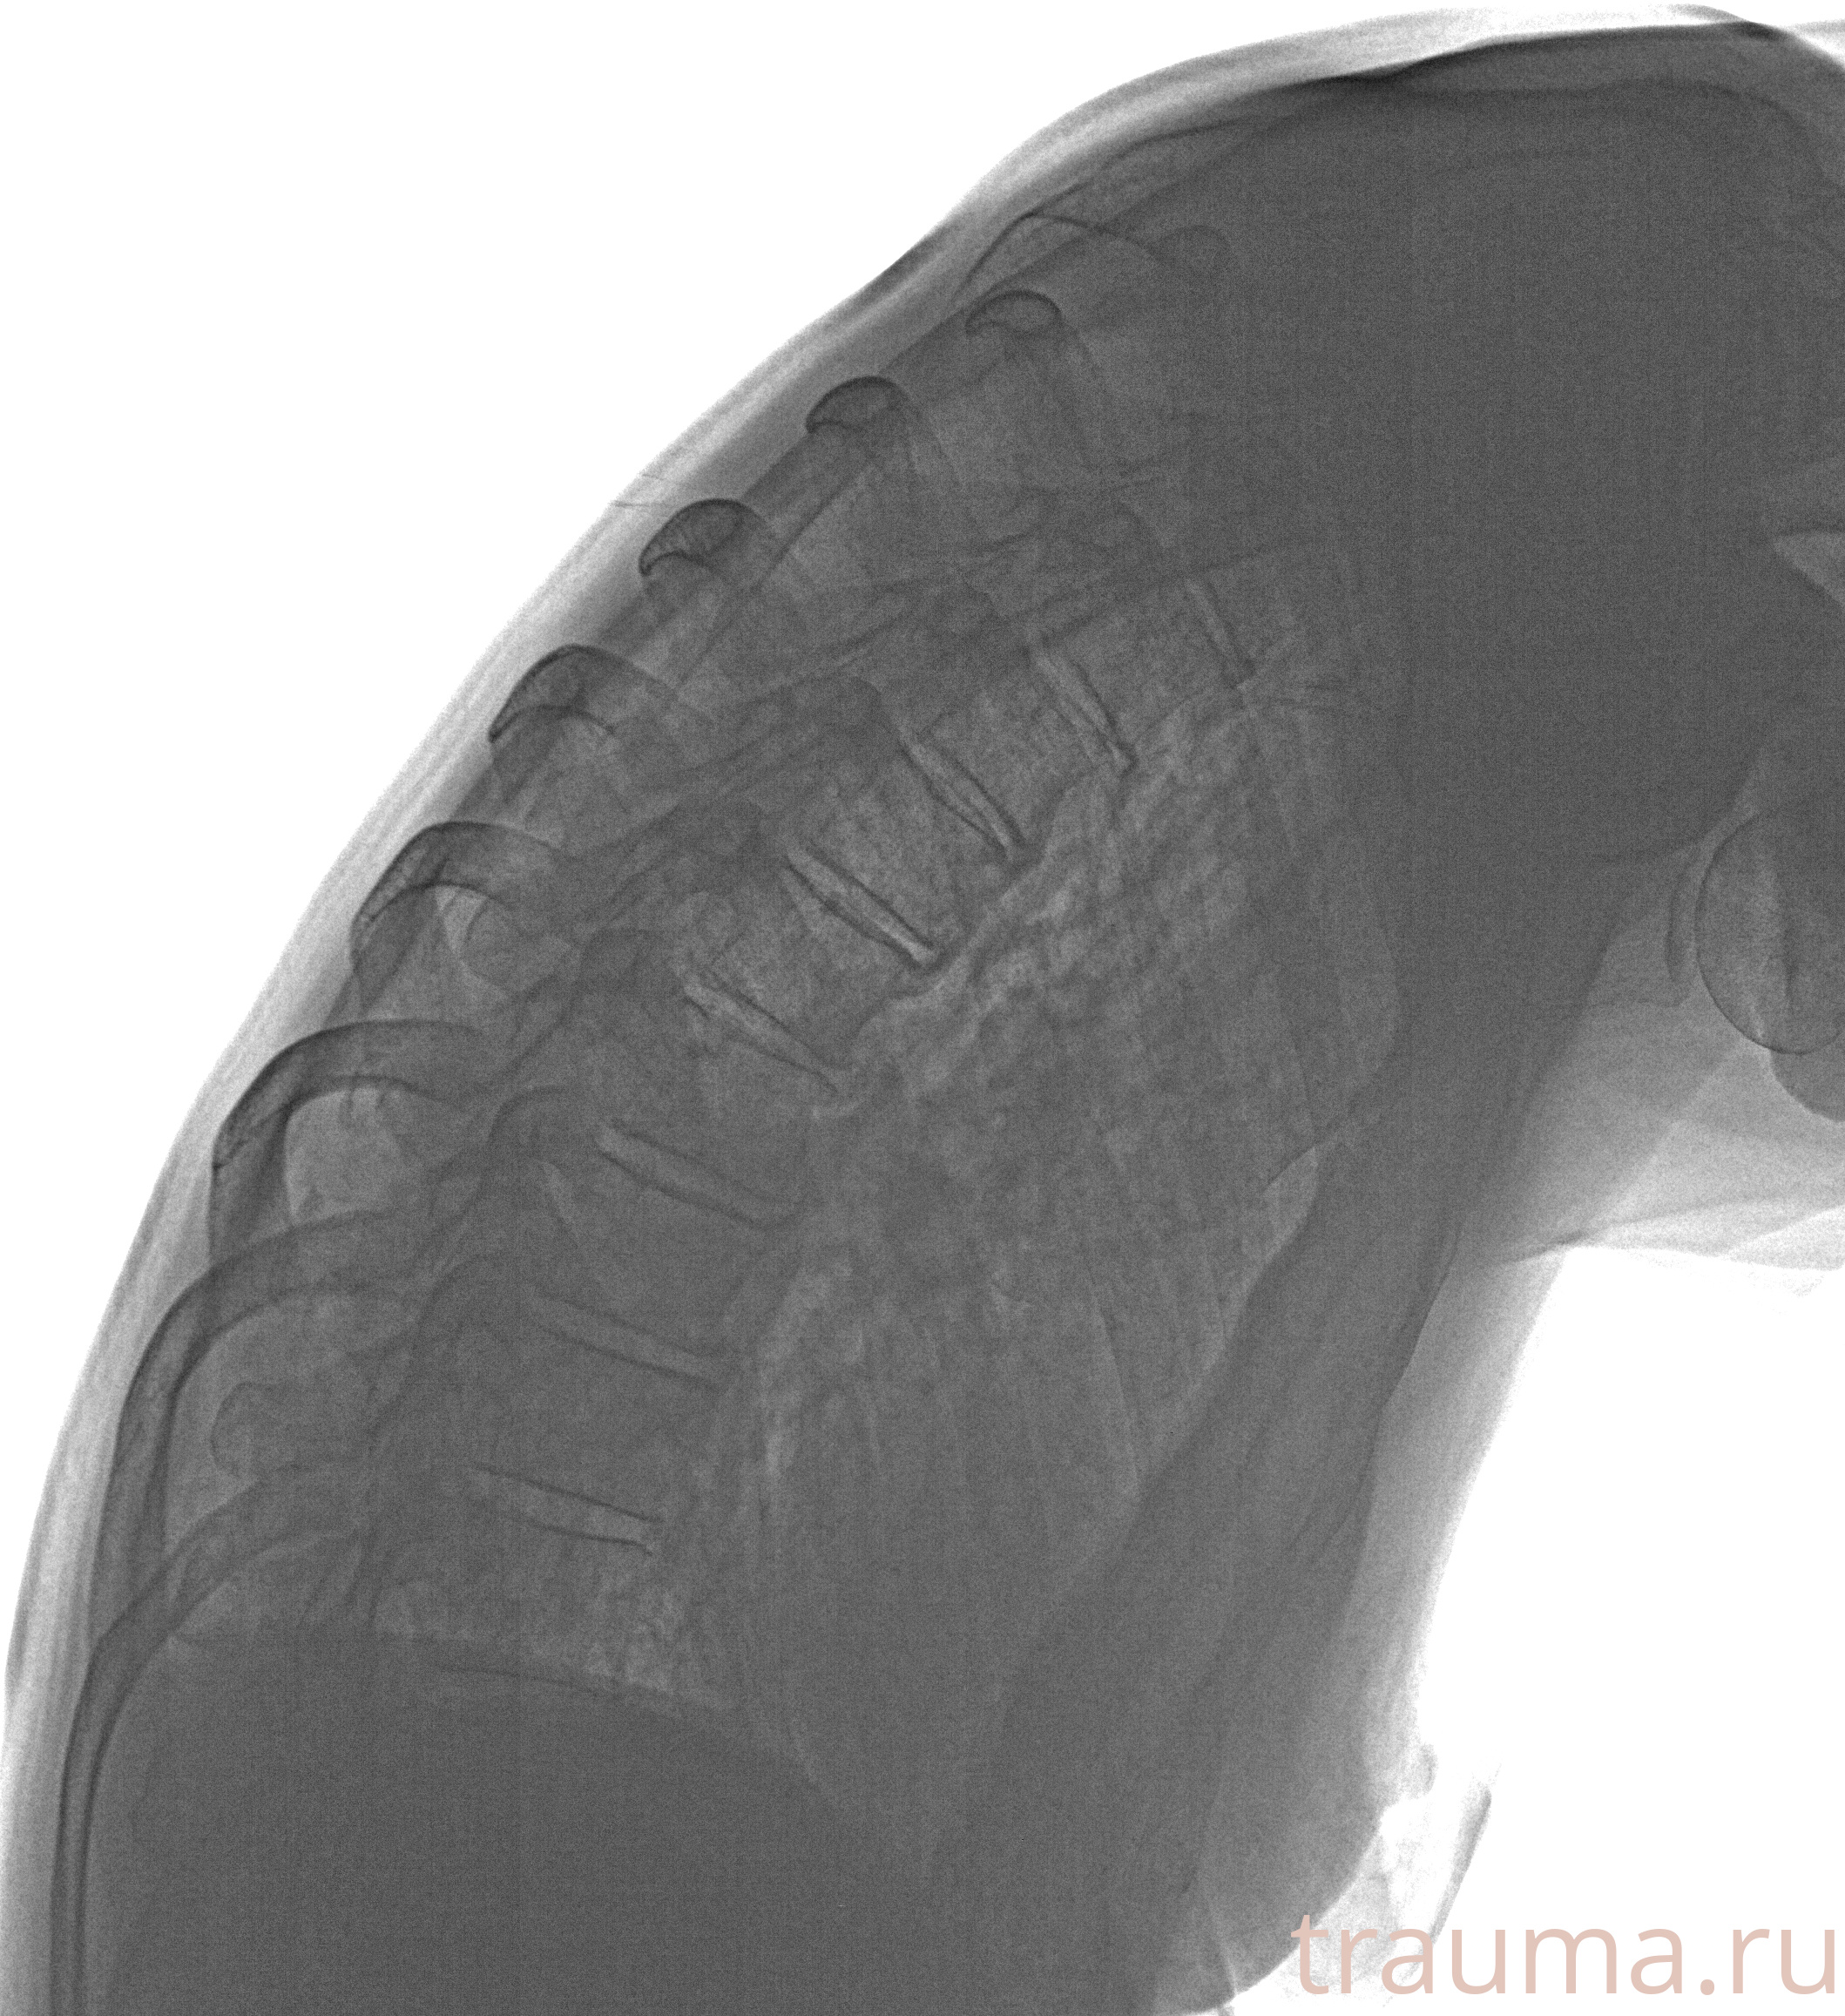

Рентгенограммы

Рентген на дому: по вашему адресу приезжает врач-рентгенолог, травматолог-ортопед с мобильным рентгеновским аппаратом, проводит диагностику травмы или заболевания, делает необходимые рентгенограммы, дает рекомендации по дальнейшему лечению. Получить качественные снимки в домашних условиях возможно благодаря уникальной методике, разработанной МосРентген Центром для института  Склифосовского